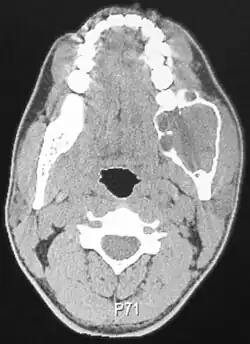

A CT scan of a patient with an ameloblastoma.

Radiographically, the tumour area appears as a rounded and well-defined lucency in the bone with varying size and features. Numerous cyst-like radiolucent areas can be seen in larger tumours (multi-locular) giving a characteristic "soap bubble" appearance. A single radiolucent area can be seen in smaller tumours (unilocular).[8] The radiodensity of an ameloblastoma is about 30 Hounsfield units, which is about the same as keratocystic odontogenic tumours. However, ameloblastomas show more bone expansion and seldom show high density areas.[15]

Lingual plate expansion is helpful in diagnosing ameloblastoma as cysts rarely do this. Resorption of roots of involved teeth can be seen in some cases, but is not unique to ameloblastoma.[10]